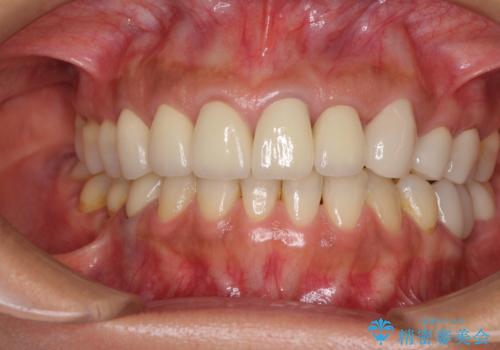

歯肉レベルを調整するために歯周外科処置をおこない、その後にオールセラミッククラウンにて補綴することとしました。

処置後の痛みはあまり気にならず、歯肉位置の左右差もほとんどなくなり、患者様には大変満足していただきました。